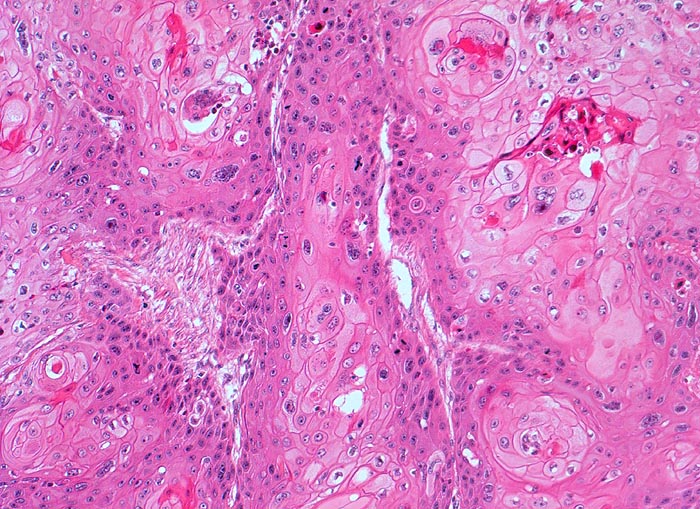

Plattenepithelkarzinom der Harnblase

Der zytologische Befund entspricht dem der Plattenepithelkarzinome an anderen Orten. Allerdings finden sich oft auffallend wenig Tumorzellen, die überdies oft nur geringe Atypien aufweisen.